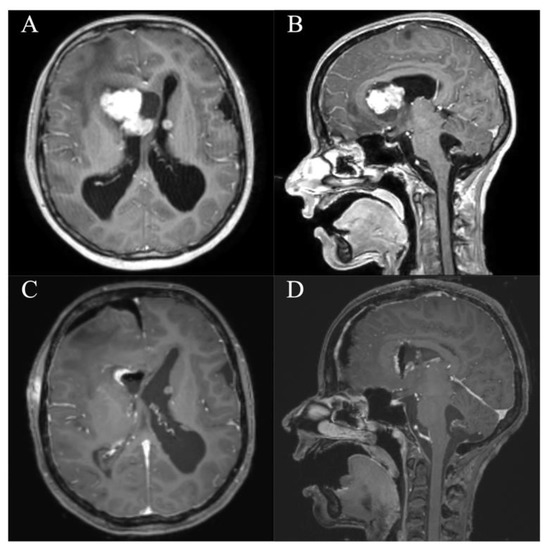

In all patients, a GTR/NTR could be achieved (Table 3). The pre- and postoperative scans of cases no. 3, 6, and 7, which were all treated through an EA approach and case no. 8, which was treated through a PE approach, are shown in Figure 3, Figure 4, Figure 5 and Figure 6. In one patient (case no. 5), due to her advanced age, we referred from resecting the vascularized capsule of the colloid cyst, achieving NTR. The mean surgery time was 163.6 ± 54.2 min (range 82–240 min) and the average blood loss was 142.5 ± 90.4 mL (range 50–300 mL). The PE approach was associated with lower mean blood loss than the EA approach (87.5 ± 47.8 mL vs. 197.5 ± 93.2 mL, p = 0.114). In four patients (50%), a total of six postoperative complications occurred, of which all were transient. Two patients (25%) showed transient cognitive impairments after resection of a colloid cyst, most likely directly associated with the endoscopic approach. The remaining four transient complications were unrelated to the use of endoscopy or NUA (Table 3). The two patients with neuropsychological evaluation showed postoperatively scores of 18/30 and 25/30 points, respectively, with a documented improvement in both patients at follow-up (18/30 to 24/30 points within 35 days and 25/30 to 30/30 points within 114 days). With regards to the remaining adult patients, no evaluation was carried out, because there was no evidence of neurocognitive deficits subjectively. In the two children with intraventricular lesions, no postoperative neurocognitive assessment was performed (due to autism disorder in the context of tuberous sclerosis in one case and due to the very young age of 5 months in the other case) (Table 3). At follow-up (15.9 ± 6.3 months; range 6.8 to 23.2 months), all patients showed improved or unchanged mRS when compared to the mRS at discharge. Complete regression or improvement of the preoperative complaints was seen in all patients, while MRI at follow-up showed no recurrence in any of the cases (Table 3).

Figure 5. Case 7. Axial and sagittal MR images, T1-weighted sequences with contrast medium preoperatively (A,B) and immediately postoperatively (C,D) after resection of the intraventricular subependymal giant cell astrocytoma via a right frontal endoscopic-assisted approach. It shows a gross total resection with residual blood in the resection cavity. Furthermore, there are pre-existing subependymal tuberosities in both lateral ventricles.